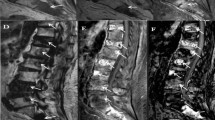

Two examples of malignant VBMLs. Upper row (a–e): histopathologically confirmed breast cancer metastasis and pathologic vertebral fracture of the thoracic spine. Lower row (f–j): biopsy proven pathologic fracture of the thoracic spine due to renal cancer metastasis. Sagittal T1-weighted SE images (a, f), DW images with b = 0 s/mm2 (b, g) and b = 800 s/mm2 (c, h) and the corresponding ADC (×10−6 mm2/s) (d, i) and PDFF (%) (e, j) parameter maps with exemplary ROI measurements. Both ADC and PDFF correctly identified metastatic lesions as malignant